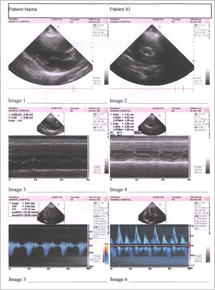

The Echocardiography done on 2nd Nov. 2006 done on Manipal Hospital clearly states Bicuspid and Thickened Aortic Valve, Mild Aortic Stenosis, Concentric LV Hyper trophy. But patient condition from 2nd Nov. to 2nd DEC had already deteriorated and she was supposed to be admitted in the Hospital By 15 th DEC. 2006

The Echocardiography report of 2nd Nov. 2006 is shown in fig 1

FIG 1:- Echocardiography report of 2nd Nov. 2006